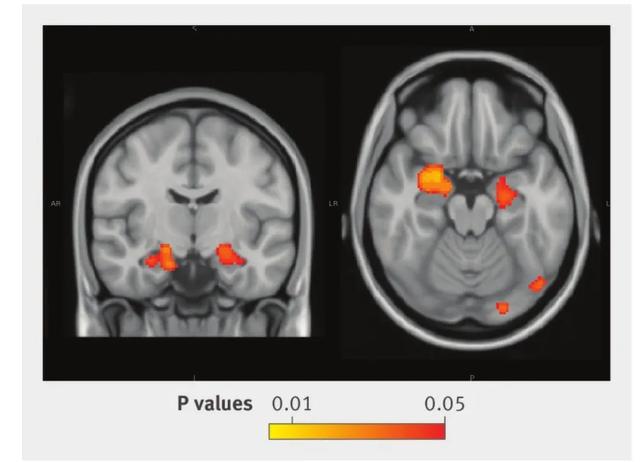

研究发现,研究期间的平均饮酒量(单位/周)与基于体素的形态测量学分析的大脑灰质密度呈负相关,特别是在海马(下图),即使在对多种潜在混杂因素进行调整后也是如此。这种影响也延伸到杏仁核的前部,但额叶区没有受到影响。